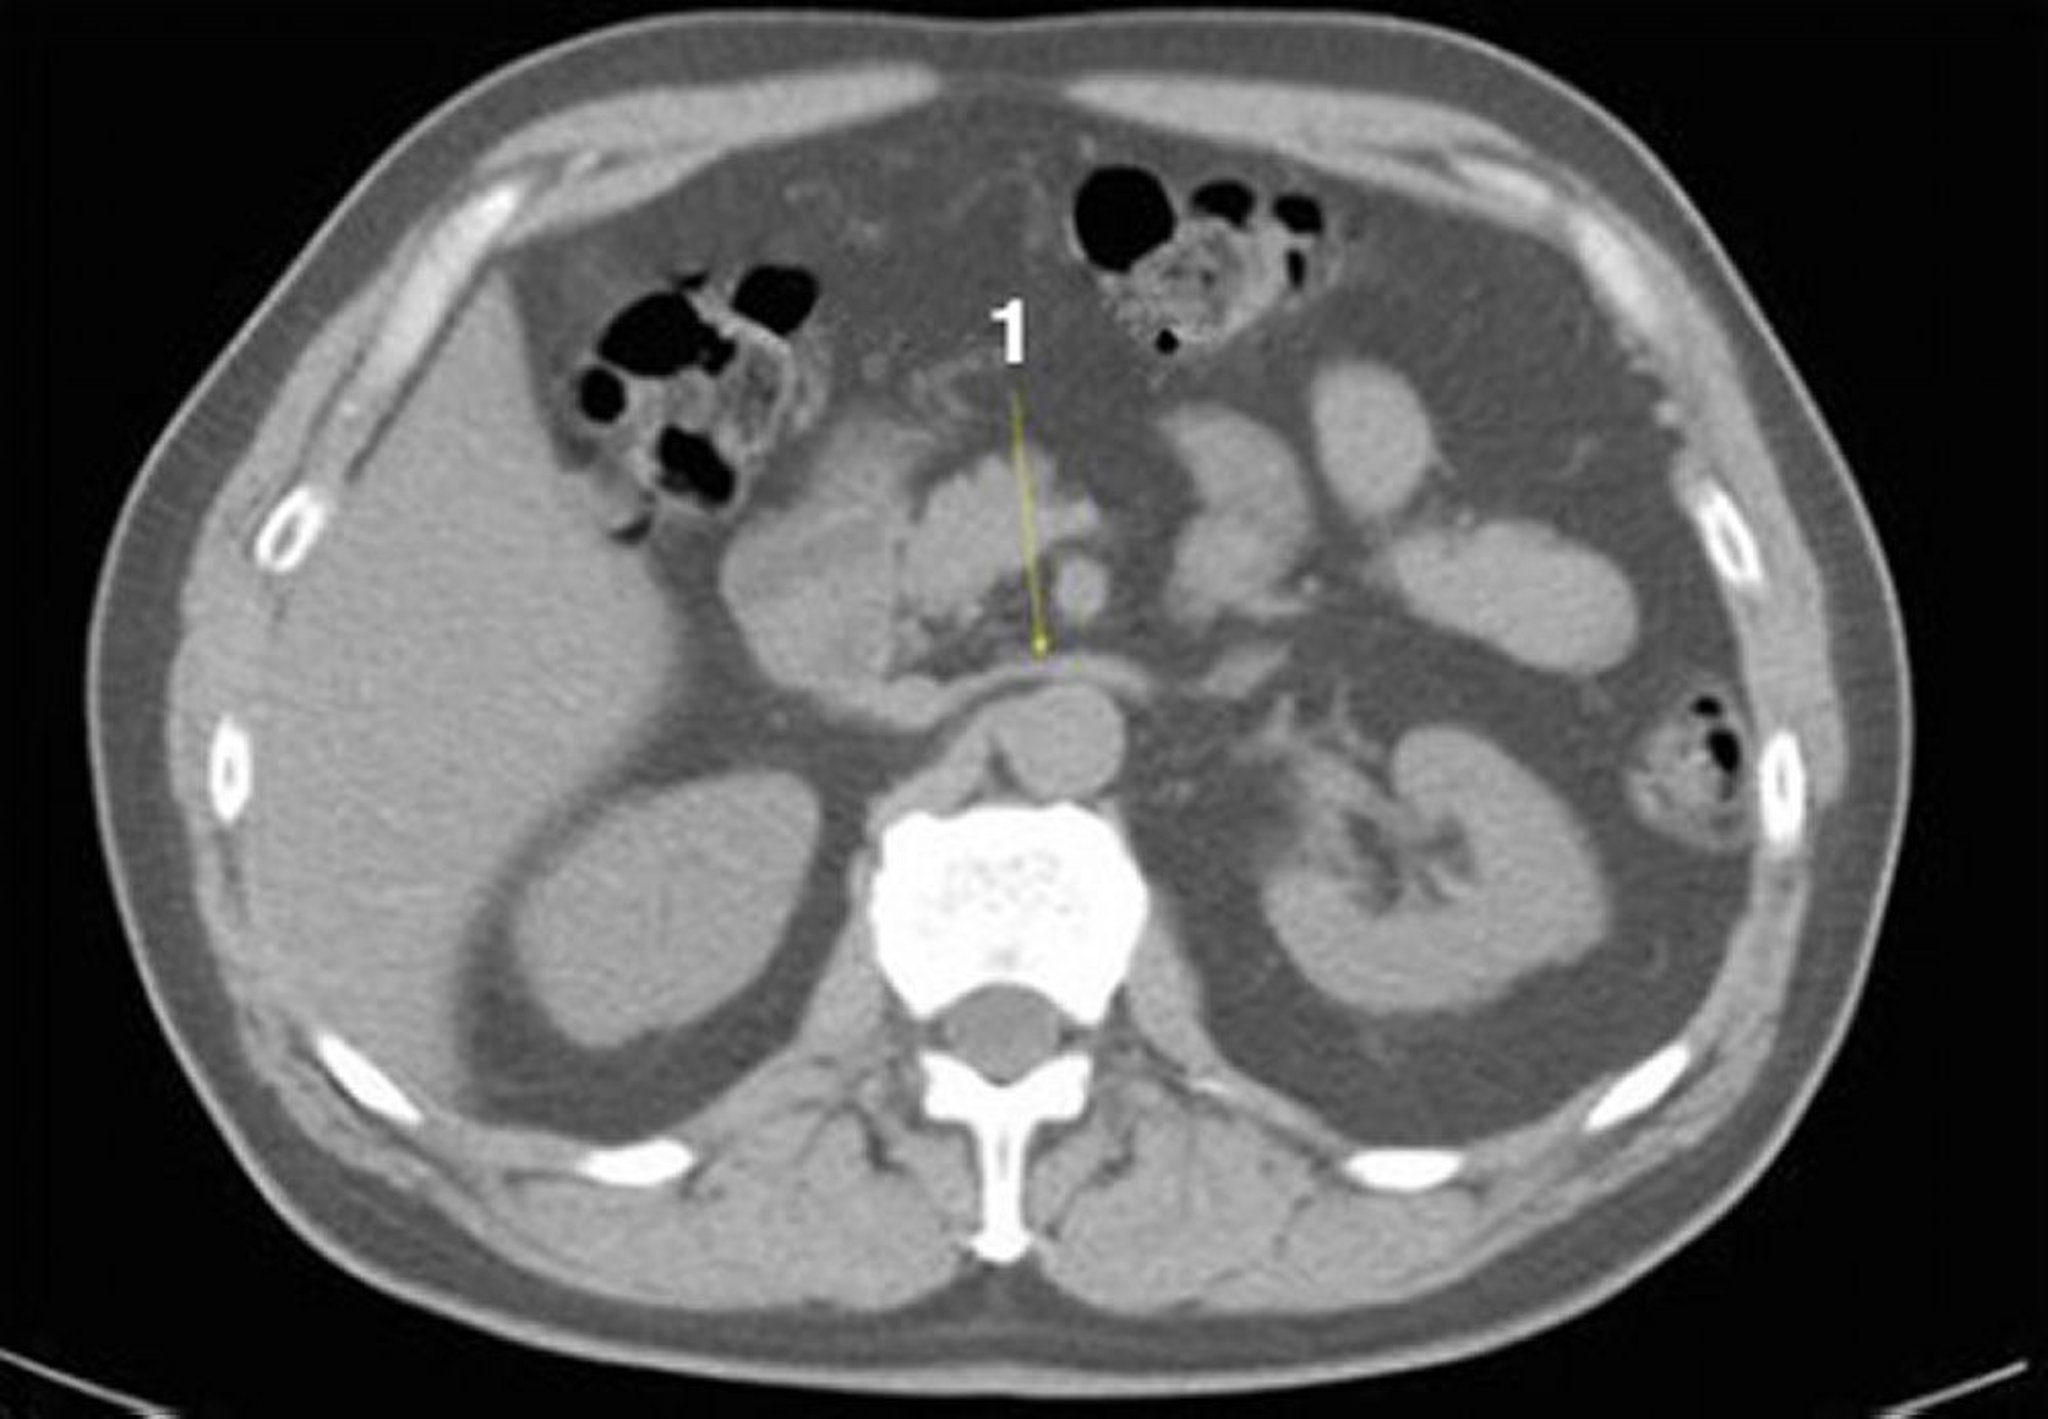

Tomografía computarizada sin contraste de abdomen y pelvis que muestra anatomía normal (corte 12)

1 = vena renal izquierda.